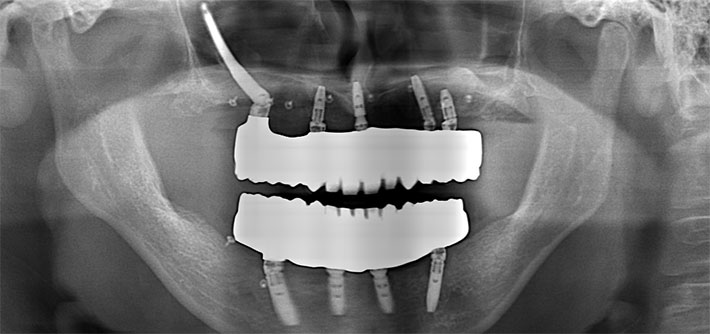

Postoperative Diagnosis治療終了時

パノラマX線

上顎CT

術前の3Dシュミレーションと治療終了時のインプラントポジションを重ね合わせると、計画通りにインプラントが埋入されている事が確認出来る。インプラントポジションの良し悪しは、インプラントの寿命を左右します。補綴から決定された、最適なインプラントポジションは、患者さんにとって永く快適にインプラントライフを過ごして頂く為の重要な要素であります。術前の診査診断と治療計画の立案、術前治療等のステップを確実に行う事で、安全で正確なインプラント治療が可能となります。

最終補綴 (上下顎:フルジルコニアタイプ)